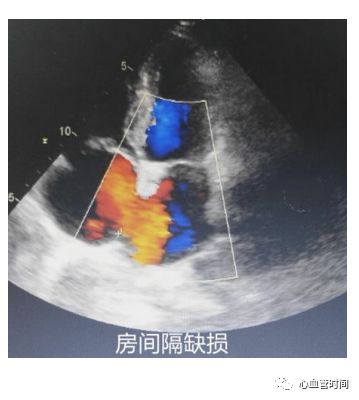

房间隔观察有无过隔血流、膨出瘤及摆动现象。一定要注意区分右房内的

红色血流是起源自下腔静脉还是房间隔,避免误诊。

三尖瓣观察三尖瓣形态及反流情况。

房间隔观察有无过隔血流、膨出瘤及摆动现象。一定要注意区分右房内的

红色血流是起源自下腔静脉还是房间隔,避免误诊。

房间隔当存在

房间隔缺损时,过隔血流因几乎垂直于探头而不易观察,建议可稍微

偏转探头调整血流角度进行观察。

房间隔当存在

房间隔缺损时,过隔血流因几乎垂直于探头而不易观察,建议可稍微

偏转探头调整血流角度进行观察。